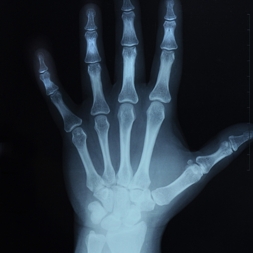

Los aparatos de última generación, como el disponible en nuestra Unidad de Densitometría, estudian fundamentalmente partes distales del esqueleto como huesos del antebrazo o falanges de los dedos. Con ello, manteniendo la misma precisión y fiabilidad, se gana en rapidez y comodidad para el paciente con repecto a los aparatos tradicionales que estudian la columna o las caderas. Además, al ser menor tanto la región a estudiar como el tiempo necesario para llevar a cabo el examen, se consigue también disminuir hasta niveles prácticamente inapreciables la cantidad de radiación que recibe el paciente.

Así pues, en nuestra Unidad de Densitometría disponemos de los medios técnicos necesarios para poder realizar de una forma altamente fiable y precisa, a la vez que con una gran rapidez y comodidad (sólo hace falta colocar adecuadamente la mano del paciente en el aparato) la valoración de la Densidad de la Masa ósea de la paciente y así poder determinar si presenta o no OSTEOPOROSIS y el grado de la misma.